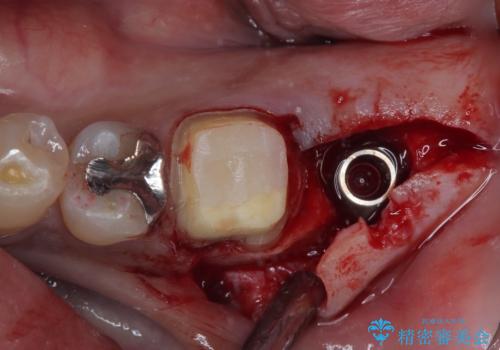

歯根が破折した歯は抜歯となるため、抜歯して病変の部分に骨が回復するのを待って、インプラントによる補綴治療を行うこととしました。

インプラント治療まで待機している間に、手前のむし歯処置されている歯が強い痛みに襲われ、確認したところ、既に神経組織が壊死している状態であったため、根管治療を行い、インプラント部と合わせて補綴治療を行いました。